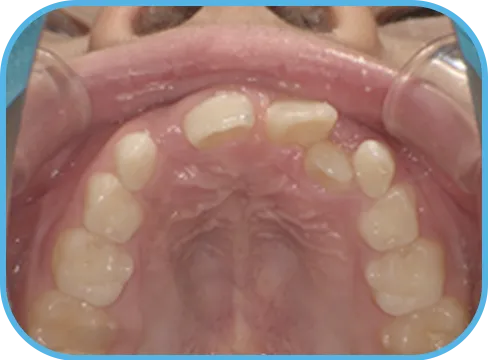

• Before

• 上 顎

治療前上顎からの歯の様子

主 訴

上の前歯がねじれている、ガタガタ

治療内容

インビザライン・ファースト

治療期間

8か月

治療費(税別)

450,000円+診断料50,000円

リスク・副作用

• 親知らずの影響や加齢などによって、凸凹が生じる可能性があります。

• 治療の初期段階では痛みや不快感が生じやすくなりますが、1週間前後で慣れます。

• 顎の成長発育によって、噛み合わせや歯並びが変化する可能性があります。

• 状況により当初予定した治療計画を変更する可能性があります。